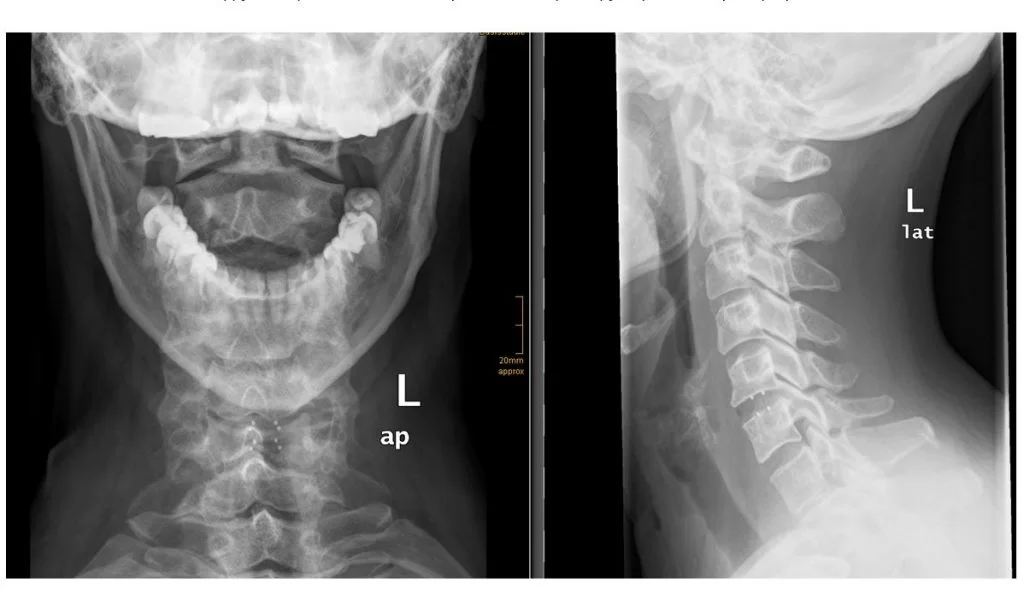

Η τοποθέτηση τεχνητού δίσκου έχει σαν στόχο να διατηρήσει την κίνηση των σπονδύλων και να αποτρέψει την εκφύλιση σε άλλα επίπεδα του αυχένα. Η διαδικασία είναι παρόμοια με την κλασσική πρόσθια αυχενική δισκεκτομή (ACDF), ωστόσο, αντί για έναν σταθερό κλωβό, τοποθετείται ένας τεχνητός δίσκος, δηλαδή ένα εμφύτευμα που διατηρεί την κίνηση (Εικόνα 1).

Εικόνα 1. Αριστερά: Σχηματική απεικόνιση εκφυλισμένου δίσκου με πίεση και ερεθισμό των αυχενικών ριζών. Δεξιά: Ο εκφυλισμένος δίσκος αντικαταστάθηκε με τεχνητό.